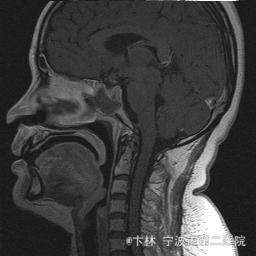

40岁女性,因“双眼视力下降三月余伴停经1个月余”入院。 患者三月前无明显诱因下出现双眼视力下降,视物模糊,尤以左眼为甚,只能近距离看到手动,无头痛、头晕,无恶心、呕吐,无视物旋转,无行走困难等不适,患者曾在某眼科医院就诊治疗,考虑为双眼视神经炎,予以营养,补液对症等治疗(具体不详),情况不见好转,近一月来患者月经停止,来我院神经外科门诊,予以查头颅CT,头颅MRI,提示“垂体大腺瘤”,为求进一步治疗收住入院

予以完善血,尿,粪常规检查,及凝血功能全套,输血功能全套及垂体功能全套,蝶鞍冠状CT等术前检查措施,行经蝶入路垂体瘤切除术。术后予以对症,补液,调节血电解质等治疗,患者视力明显改善,复查头颅MRI提示肿瘤基本全切,一周后患者出院。

此病人颅内垂体瘤体积较大,突破鞍隔压迫视交叉,故患者视力视野障碍为首发症状,该肿瘤主体有大部分向蝶窦腔生长,因此采用经蝶手术入路,肿瘤切除满意,术后患者视力视野恢复满意,。